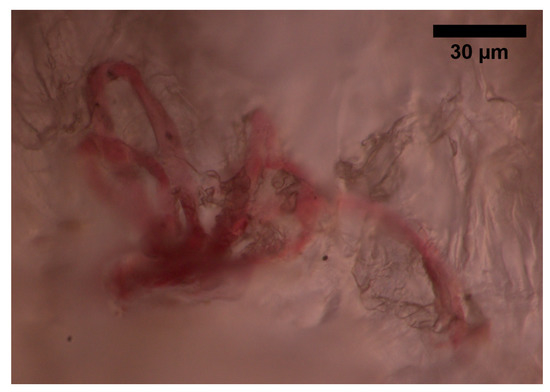

- The superficial vascular plexus, which is a network of blood vessels located at the uppermost level of the dermis. From a histological point of view, this plexus marks the junction between the papillary and reticular dermis. The superficial plexus is composed of anastomosing small-calibre arterioles that branch off into capillaries, which extend into dermal papillae to supply the boundaries between the epidermis and dermis and envelop adnexal structures [60]. Each dermal papilla is provided with at least one capillary loop [58]. In Figure 4, an image of a pig skin sample—obtained through a 50× microscope objective and a lateral scan at different depths—shows an example of a capillary loop.

Figure 4. Image of a capillary loop from a sample of pig skin obtained with an optical microscope and an M-Plan APO 50 × 0.55 NA microscope objective.